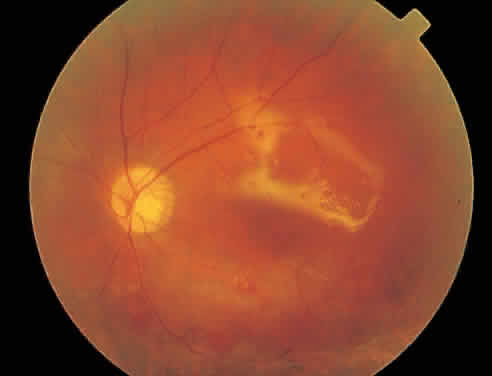

Fig. 11. Active cytomegalovirus retinitis just inferior to the macula. The visual acuity is 20/30 (6/9).

Fig. 12. Three months after implantation of an intravitreal sustained-release ganciclovir implant, the retinitis is completely healed and the vision is 20/25 (6/7.5).